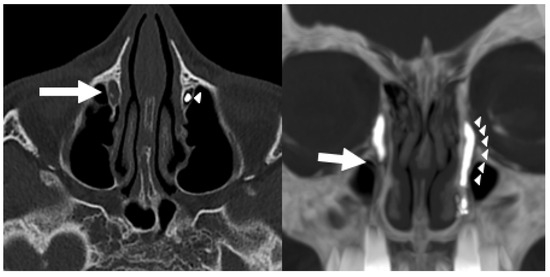

Background: Conventional CT–dacryocystography (CT-DCG) requires canalicular cannulation and forced contrast injection, which may distort anatomy and cause discomfort. This study describes a non-cannulated CT-DCG protocol using dropwise iodixano...